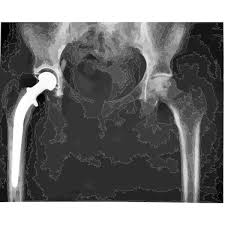

걸음걸이 변화와 절뚝거림

고관절 통증이 지속되면 자연스럽게 걸음걸이가 달라지는 경우가 많습니다.

• 한쪽 다리에 체중을 싣기 어려움

• 절뚝거리며 걷게 됨

• 보폭이 짧아짐

• 오래 걷기 힘들어짐

이러한 변화는 몸이 통증을 피하려는 보상 작용으로 나타나며, 장기적으로는 허리나 무릎 통증으로 이어질 수 있습니다.